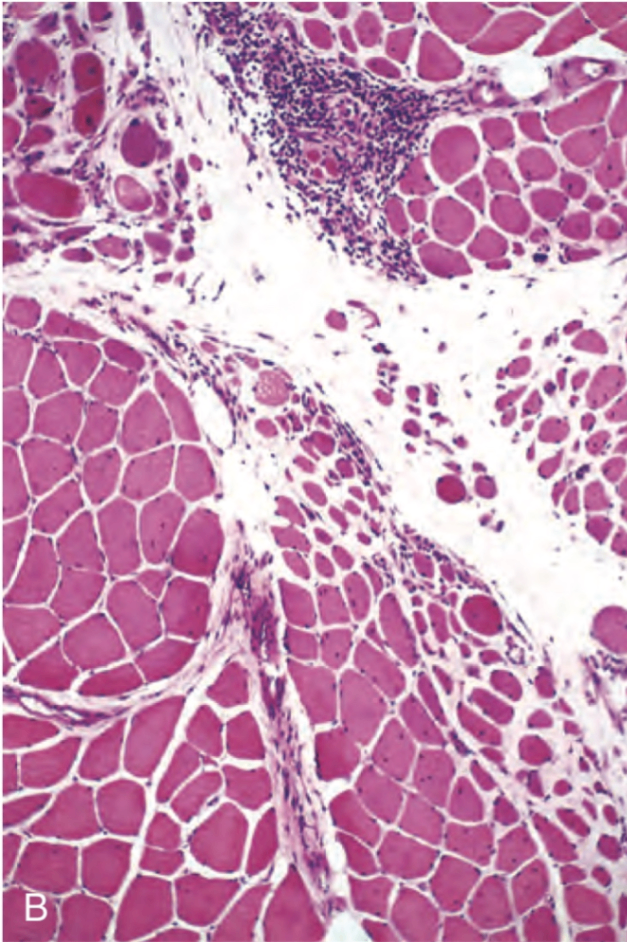

(2) 조직학적 소견

• monoculear inflammatory cell, 특히 CD4+ T cell이 perimysial connective tissue에 침윤

perifascicular atrophy가 관찰됨

Robbins and Cotran Pathologic Basis of Disease, 10e, pg 1229